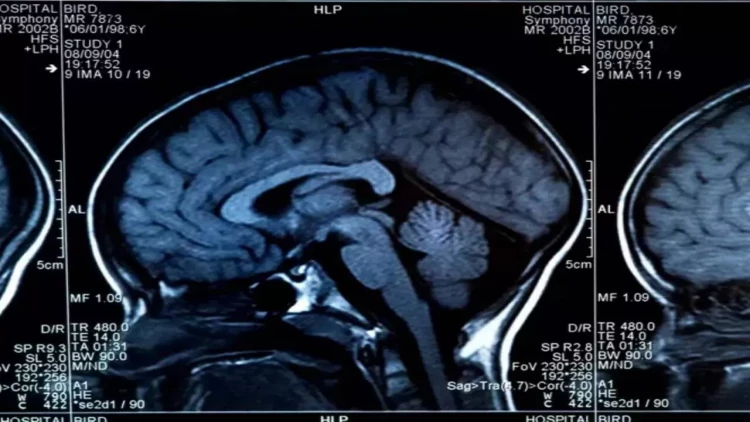

Beynin sağlamlığını təhlükəyə atan 8 qida açıqlanıb.